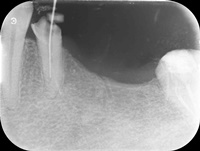

Pacjentka zgłosiła się z bólem. Kilka miesięcy wcześniej leczona kanałowo lewa dolna szóstka. Ząb wrażliwy na nagryzanie. Podjęto decyzję o ponownym przeleczeniu kanałów korzeniowych. Zamknięto perforację przy wejściu do dalszego kanału, usunięto złamaną igłę lentulo z dalszego kanału, udrożniono mezjalne kanały, aż do perforacji korzenia w policzkowym bliższym kanale. Wypełniono dalszy kanał gutaperką, bliższe kanały wypełniono MTA. Ząb do obserwacji, najprawdopodobniej będzie wykonana resekcja wierzchołków bliższego korzenia, na poziomie perforacji.

Reendo 46.